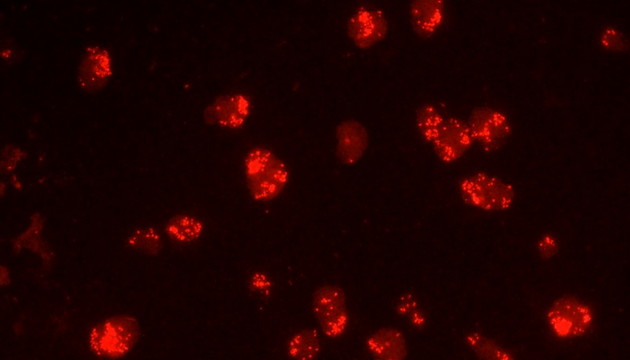

熒光原位雜交(Fluorescence In Situ Hybridization,FISH)是臨床病理檢測中廣泛運用的一種分子細胞遺傳學診斷技術,其原理是用熒光染料直接或間接標記的DNA核酸探針與待測樣本中的DNA核酸序列按照堿基互補配對的原則進行雜交,然后通過熒光顯微鏡觀察熒光信號位置、數量等來判斷待測序列的缺失、擴增及易位等情況。其高分辨率、直接反映異常細胞比例、快速簡便的特點,使其成為臨床檢測、預后評估及用藥指導的重要工具。

FISH技術面臨熒光弱、背景噪聲、多通道疊加等難點。為了保障熒光信號強度,一般需要用到研究級熒光顯微鏡,半復消色差或以上的物鏡,以及高功率的LED熒光光源或汞燈光源;為了去除背景噪聲,一般需要搭配高截止深度的濾光片和高靈敏度相機;多通道疊加時要提取紅綠信號點,然后放到藍色DAPI信號上,處理需要相當的技巧。